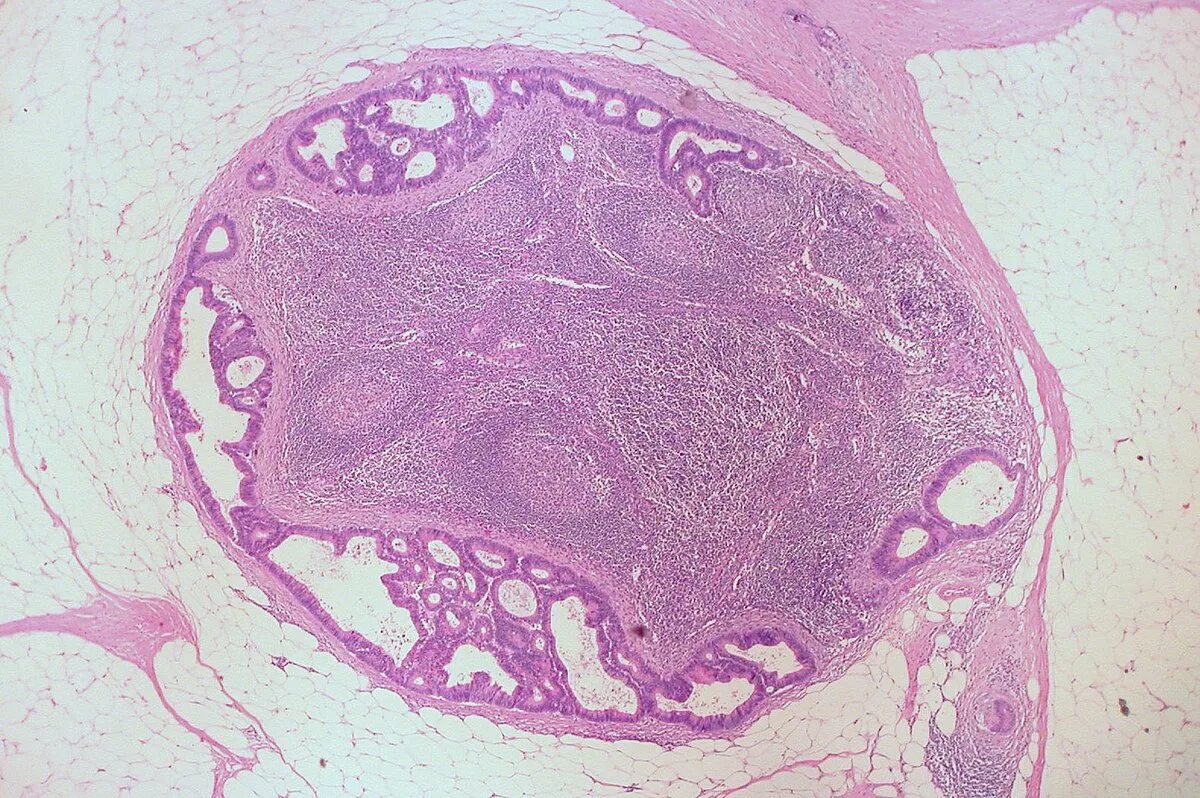

Метастазы в лимфоузлах молочной железы